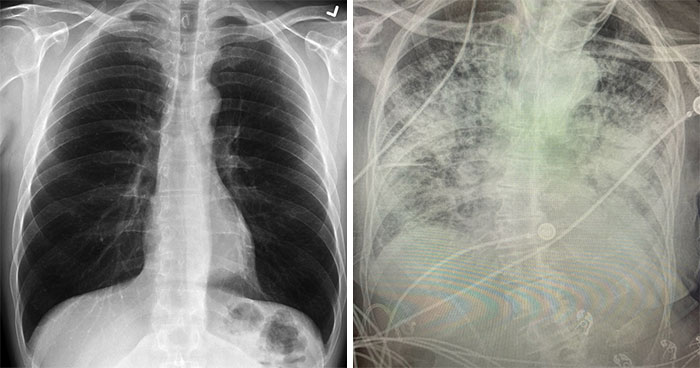

Even after a whole year of fighting this deadly virus, there’s a devastating amount of things we still have yet to find out about COVID-19 and its long-term effects on a person’s health. However, recently, a doctor from Texas, who’s treated thousands of COVID patients since March, shared some valuable insights on the disease and its consequences after comparing three lung X-rays: one of a healthy patient, one of a smoker, and one of a COVID-19 patient.

Dr. Brittany Bankhead-Kendall, an assistant professor at Texas Tech University Health Sciences Center, went on Twitter to share that post-COVID lungs look way worse than any type of terrible smoker’s lungs she’s ever seen.

The doctor also posted photos of three lung X-rays—one of a healthy patient, one of a smoker, and one of a COVID-19 patient—to point out the differences.

The lungs of a healthy patient appear to be clear as they have a lot of black space, indicating that a person can inhale a great deal of air

Looking at the X-ray of a smoker’s lungs, you can notice some haziness indicating scarring and congestion

The third image shows post-COVID lungs which appear to be almost fully white, meaning the lungs are severely damaged

As you can tell from the X-ray comparison, post-COVID lungs can look way worse than those of a smoker

“There are still people who say ‘I’m fine, I don’t have any issues,’ and you pull up their chest X-ray and they absolutely have a bad chest X-ray,” the doctor told CBS DFW. “You’ll either see a lot of that white, dense scarring or you’ll see it throughout the entire lung. And if you’re not feeling problems now, the fact that that’s on your chest X-ray, it sure is indicative of you possibly having problems later on.”

Apparently, even asymptomatic patients show a severe chest X-ray 70 to 80 percent of the time. Dr. Bankhead Kendall also adds that if a post-COVID patient is experiencing shortness of breath, they should stay in touch with their primary care doctor.